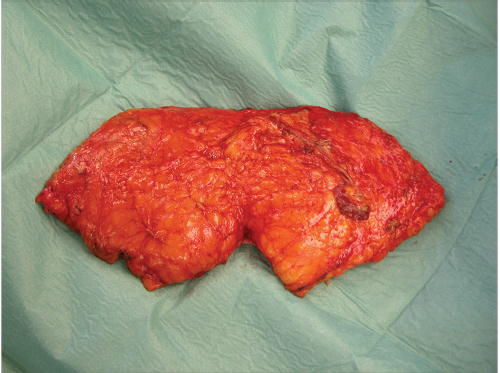

To avoid perfusion problems, especially venous congestion, we first identify the dominant perforator pulsation and course by intraoperative Doppler control (▶Fig. 54.3). We then assess the area of skin perfused by this perforator, by applying vascular clamps to all nonselected perforators. After a minimum of 5 minutes (undermining of abdominoplasty to xiphoid can be performed in the meanwhile), the capillary refill and perfusion of the flap can be rechecked and if the selected perforator is not sufficient and the flap shows signs of vascular problems such as venous congestion (▶Fig. 54.4), another perforator can be chosen, more than one perforator or an ms-TRAM can be necessary to be taken in consideration (▶Fig. 54.5).